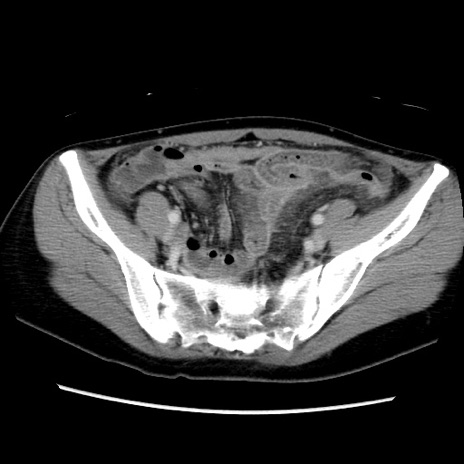

症例39(横断像)

【症例】40歳代女性

【主訴】上下腹部痛

【現病歴】2日目から下腹部痛あり。夜間は痛みで眠れなかった。昨日より上腹部痛と下痢が出現。臥位で痛みは軽快したため、休んでいた。本日になって臥位でも立位でも痛みが強くなってきたため救急要請。

【既往歴】子宮内膜症

【身体所見】部:平坦・軟、左上下腹部に圧痛あり、反跳痛あり。

【データ】WBC 21800、CRP 26.78